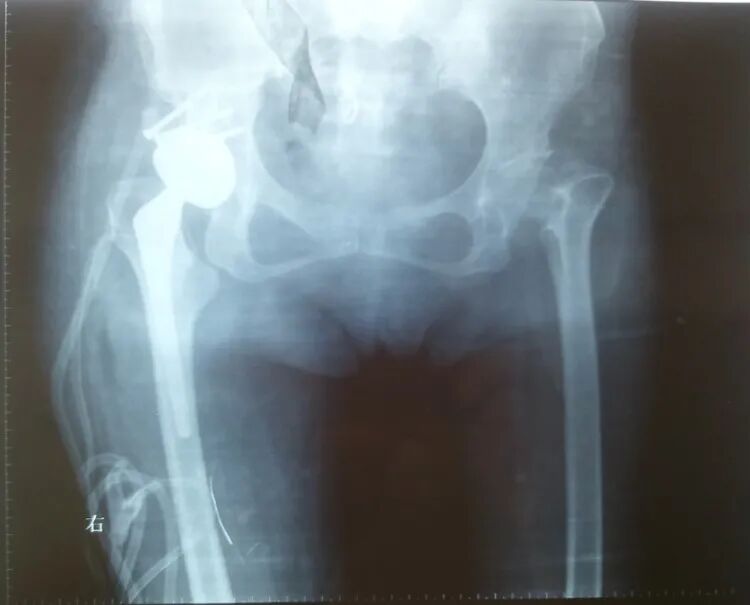

女性患者,48岁,右髋疼痛25年,加重1年

术后5天,脱位

切开复位

术后4月,再一次脱位

屋漏偏遭连夜雨